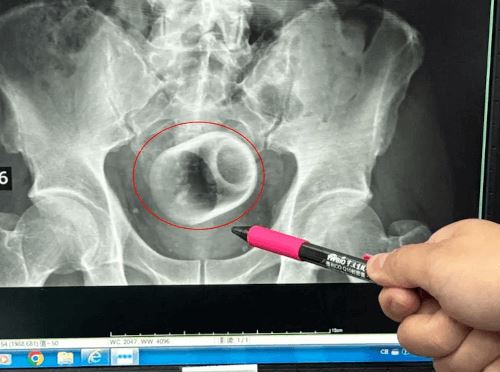

К нему обратился мужчина, три дня страдавший от вздутия живота и непроходимости кишечника. Что неудивительно, ведь в прямой кишке незнакомца застряла керамическая чашка. При этом удалять посторонний предмет пришлось с помощью открытой операции, разрезав брюшную полость и вскрыв кишечник пациента. Иначе чашку было не подцепить.